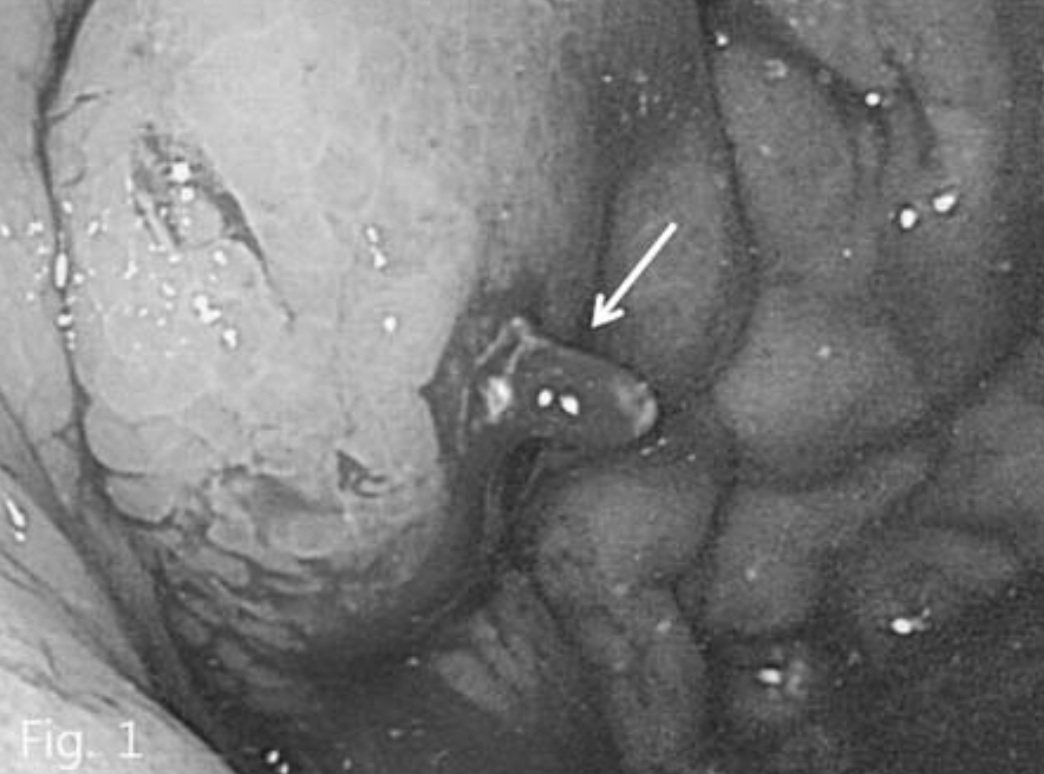

B형 간염에 의한 간경화 환자로 내원 하루 전 2차례의 토혈이 있어 내원하였다. 위내시경에서 식도 정맥류와 위정맥류가 동시에 관찰되었으며 내시경적 결찰술을 시행하였으나 그 후에도 위정맥류 부위에서는 지속적인 출혈이 있었다(Fig. 1).

Fig. 1

Endoscopy shows large gastric varices with active bleeding (arrow).